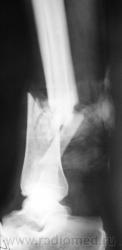

Травма. Вот, такой переломчик...

Травма.  Произведена рентгенография в стандартных проекциях.

Наверное, открытый?

Нет. Закрытый.

Здравствуйте, уважаемый Валентин Львович! Очень похож на "бамперный перелом". У меня вопрос - а почему снимки без шины? Ведь пациенту наверняка было больно при проведении исследования в двух проекциях.

Чегото на боковом структура кости не странная? Как будто в области перелома есть еще дополнительное тенеобразование..     Мягкие ткани?